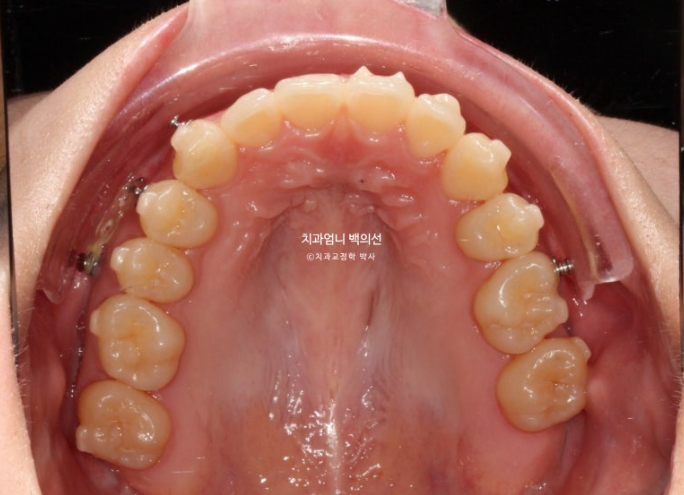

고무줄 처방으로 인해 중심선은 정확하게 맞으며

교합은 나쁘지 않습니다.

배열도 좋습니다.

웃는 사진에서는 결손치 쪽으로 돌아가 있던 윗니 중심선이 드디어 코와 인중을 만나게 되었습니다.

그러나 왼쪽 앞니 하나가 미미하게 치축이 기울어져 보입니다.

이 부분과 교합 안정화를 위해 추가장치 제작에 들어갑니다. 24년 12월부터 25년 3월까지 14개 추가장치를 다 낀 후 치료를 마무리 하였습니다.